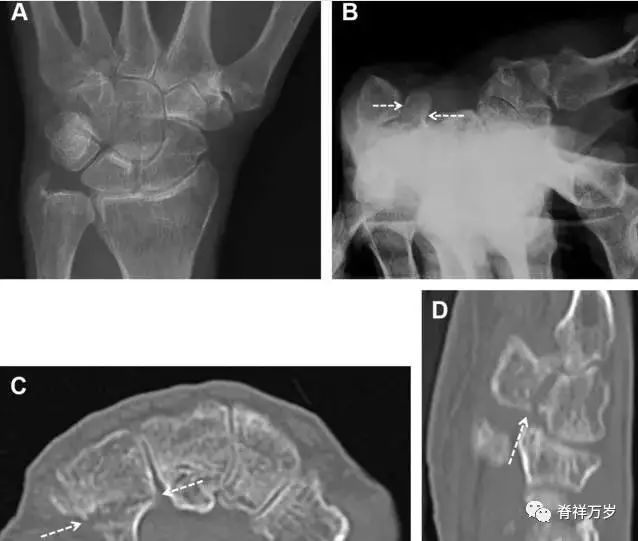

34.钩状骨骨折

钩状骨骨折可发生于体部和钩部,钩部骨折更多见,可合并有第 4、5 腕掌关节脱位。受伤机制由直接*力暴**或腕横韧带撕脱伤所致。骨折征象包括钩部无显示、骨皮质边缘模糊、硬化或双密度影等。常规的正侧位常无法明确诊断,需要加拍腕管位,可清晰显示其钩部。

图 5 打高尔夫球后腕部急性疼痛。常规腕关节 X 线片正常(X)。腕管位片(B)隐约可见钩部横行骨折(虚线箭头),CT 检查(C、D)进一步明确了诊断。